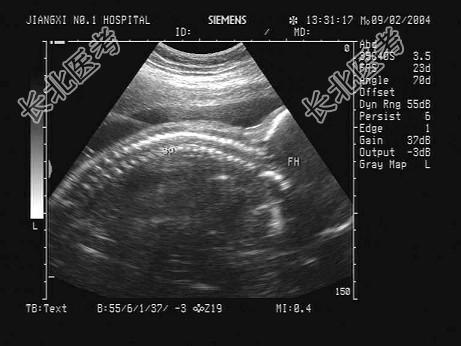

- 单项选择题根据胎儿声像图,可见清晰脊柱和头颅光环, 该胎儿至少应大于多少周   (   )

A、6周

B、8周

C、28周

D、32周

E、12周